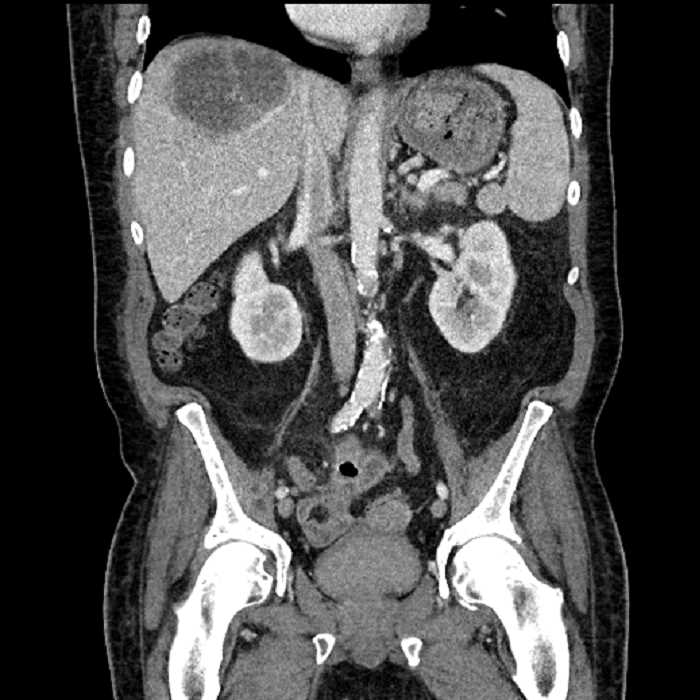

Age: 63

Sex: Male

Indication: Abdominal pain

• Large fluid density structure in hepatic segments 7 and 8 measuring 10 x 7 x 7 cm with internal septation and circumferential ill-defined low density compatible with edema

• Peripherally enhancing subcapsular collections along the anterior margin of the left hepatic lobe measuring 3 x 1 cm and 2 x 1 cm

• Clearly marginated fluid density structure in segment 7 and several other scattered tiny hypodensities, which likely represent cysts

• High grade stenosis of the left common iliac artery, with the left internal and external iliac arteries remaining patent

• Hepatic abscess

Acute sigmoid diverticulitis complicated by a small contained perforation and a large abscess in the right hepatic lobe. Additional small subcapsular abscesses along the anterior margin of the left hepatic lobe.

Additionally, loss of the normal fat plane between the peridiverticular collection and adjacent thickened loops of small bowel raises the potential for an enterocolonic fistula.

High grade stenosis of the left common iliac artery. The left external and internal iliac arteries are patent.

• The classic CT imaging appearance is a double target sign with internal low density surrounded by an internal enhancing rim (capsule) and a low density external rim (edema)

Hepatic abscess showing the double target sign with low density internally surrounded by a thin inner enhancing rim (red arrow) and ill-defined outer low density rim (yellow arrow). Blue arrow indicates an internal septation. Red arrows: additional smaller subcapsular abscesses. Red arrow: focal contained perforation associated with diverticulitis.